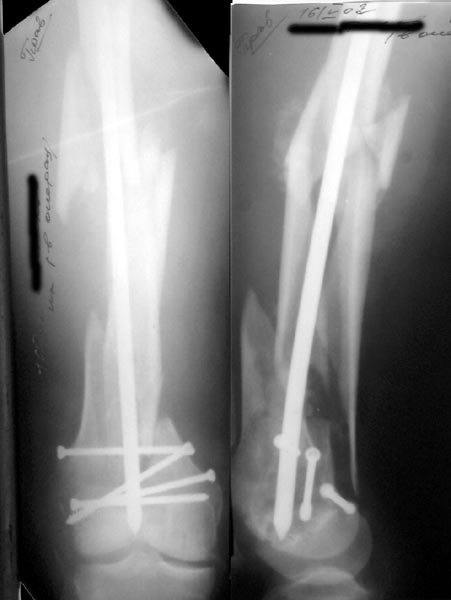

See attached case that was done several years ago before LISS. He had comminuted trochlea and anterior blocking screws were used to prevent anterior IMN cut-out.

Да, примерно так и сделали. Надо было, пожалуй, кончик гвоздя еще спилить, чтобы отверстие было еще дистальнее. Англоязычные коллеги еще

Since it was done closed the shaft will heal or at worst need an exchange IMN.

Nice job.

Мы пошли на операцию с планом попытаться сделать закрытый интрамедулярный, а не получится - сделать аппаратом. Посчитали, что получилось, хотя на еженедельной конференции ожидаются некоторые проблемы с объяснениями ;-)

Насчет стабильности для ранней нагрузки, конечно, сомнительно, но при таком повреждении ранняя нагрузка противопоказана в любом случае. Для ранних движений Должно хватить. Снимки в следующем сообщении.